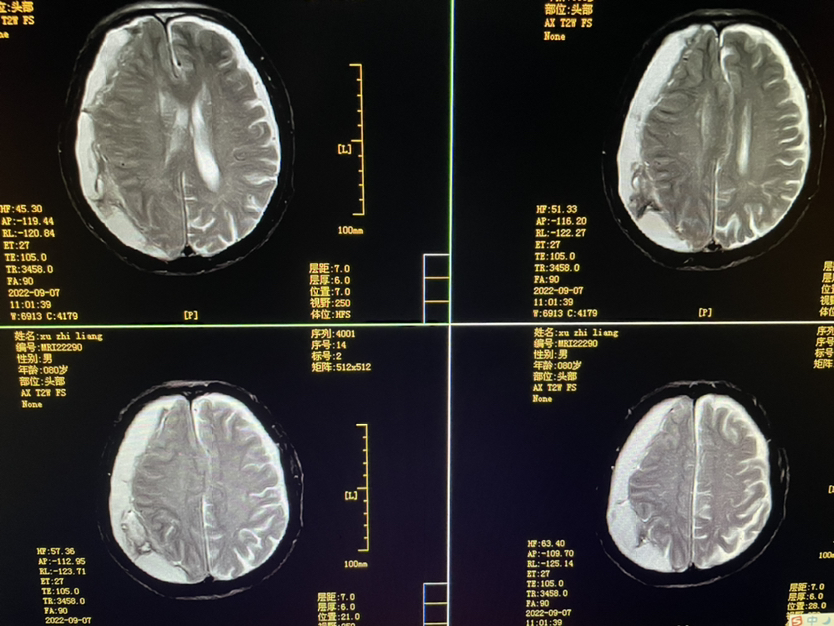

明确外伤史二月,80y,